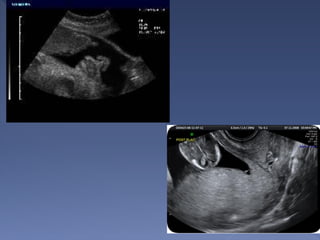

• Standard – Anatomic Survey

• Limited – Targeted to answer a question

• Specialized – Targeted anatomic

• Fetal biometry

• Fetal Cardiac Activity

• Fetal Lie

• Fetal Number

• Placental Location

• AFI

• BPP/Modified BPP

 Bi-parietal diameter

 Occipto-frontal diameter

 Head circumference

 Abdominal circumference

 Femur length

 All can be + or – 2 weeks